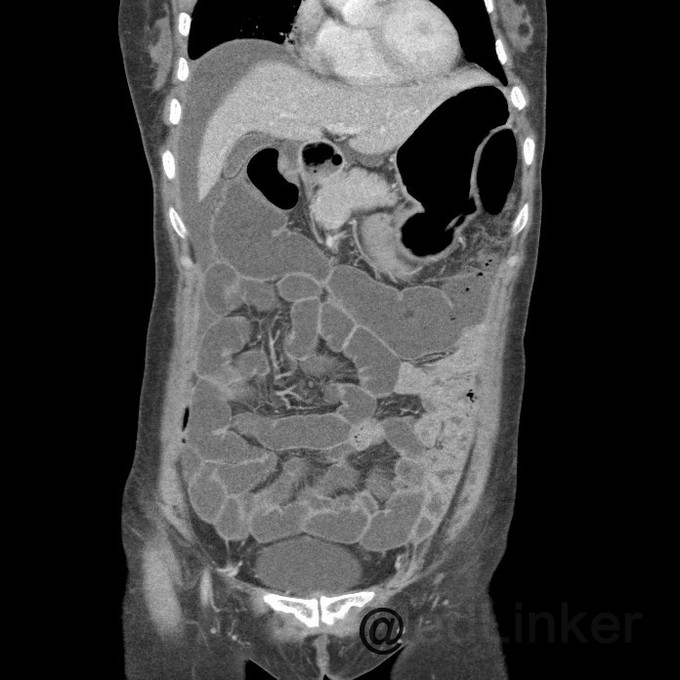

问题:患者女,50岁,因腹胀而就诊,遂行胸腹CT,提示:腹部大网膜、小网膜区脂肪间隙模糊,腹膜增厚,可见片絮状、小结节状软组织密度影,增强扫描见轻度强化。考虑转移癌可能性大。后行大网膜活检,病理结果提示:低分化转移癌。但全身PET/CT未见原发灶,此种情况下,常考虑原发灶在那些部位,以及进一步做什么检查?